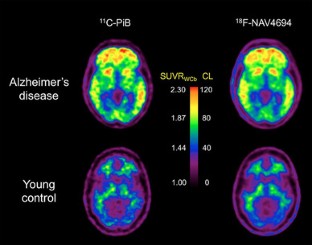

Klunk WE, Koeppe RA, Price JC, Benzinger TL, Devous Sr MD, Jagust WJ, et al. The Centiloid Project: standardizing quantitative amyloid plaque estimation by PET. Alzheimers Dement. 2015;11:1–15.

- 55.

Rowe CC, Jones G, Doré V, Pejoska S, Margison L, Mulligan RS, et al. Standardized expression of 18F-NAV4694 and 11C-PiB β-amyloid PET results with the Centiloid Scale. J Nucl Med. 2016;57:1233–7.

- 56.